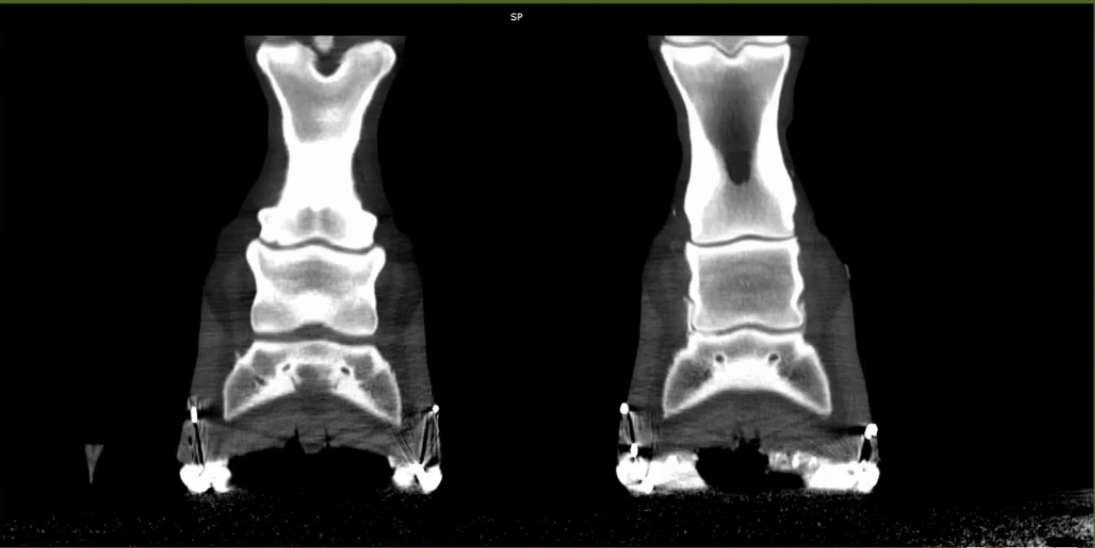

Image Gallery

Case Studies